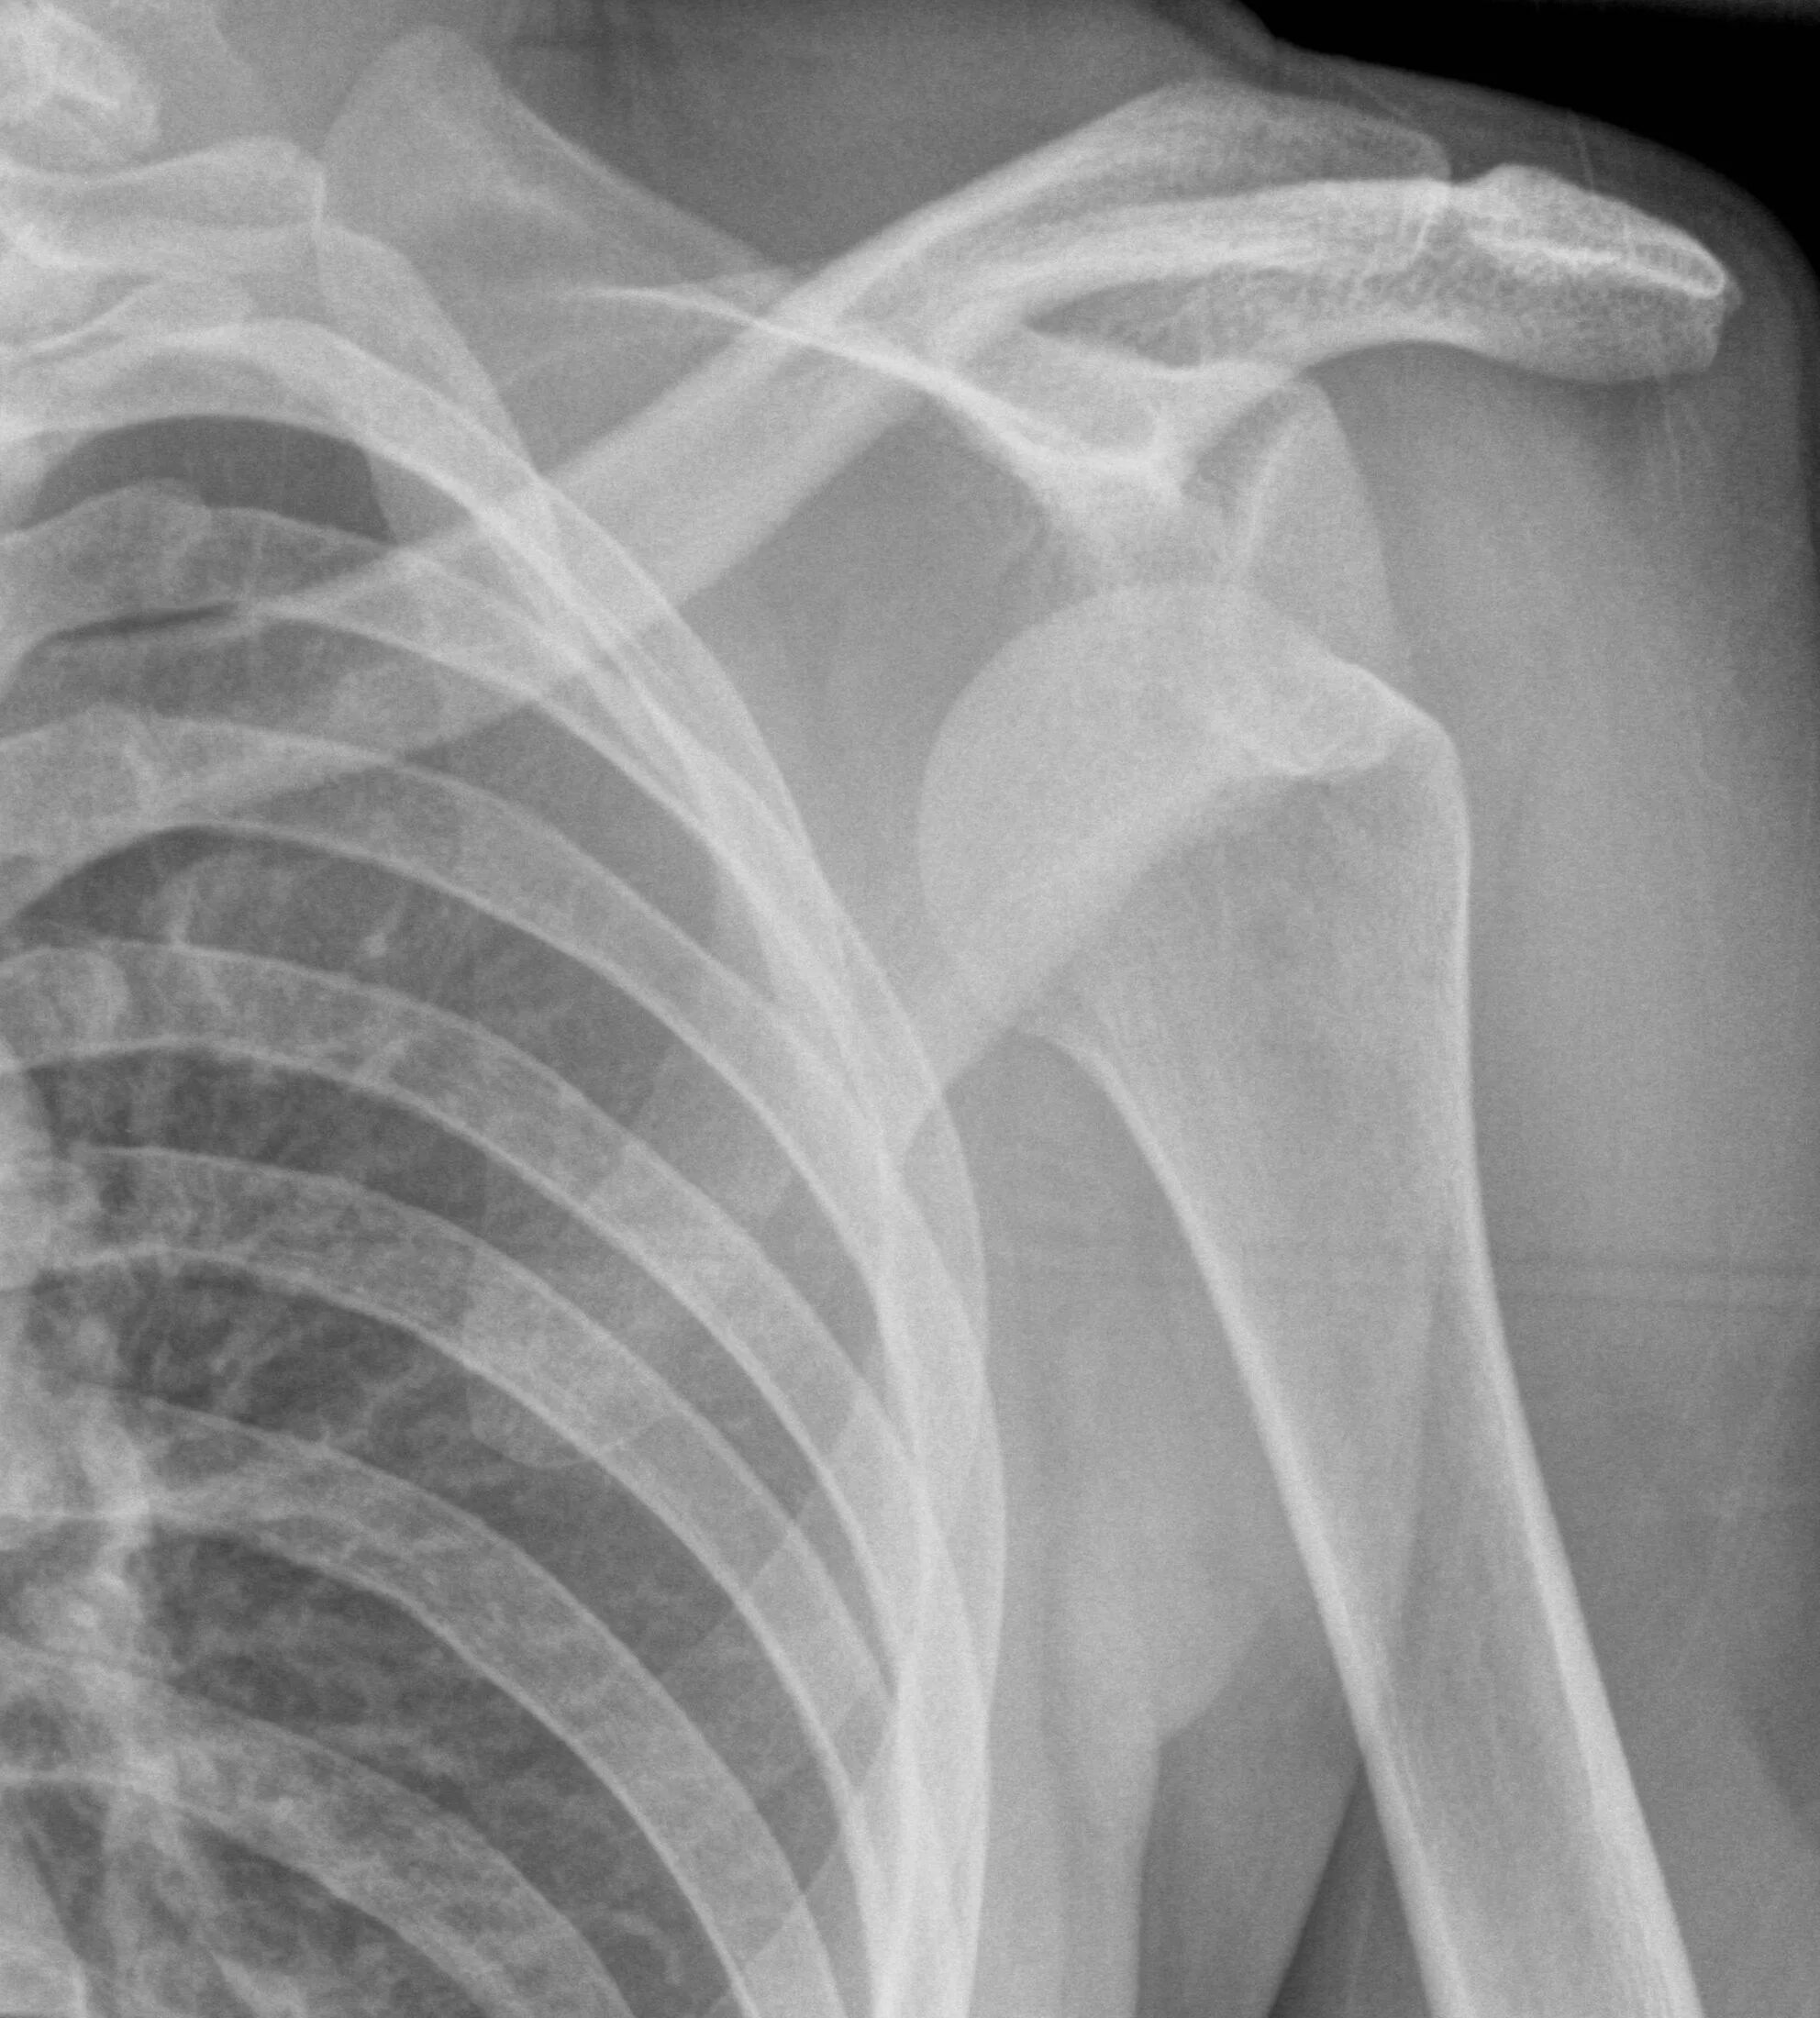

Как долго заживает вывих плеча